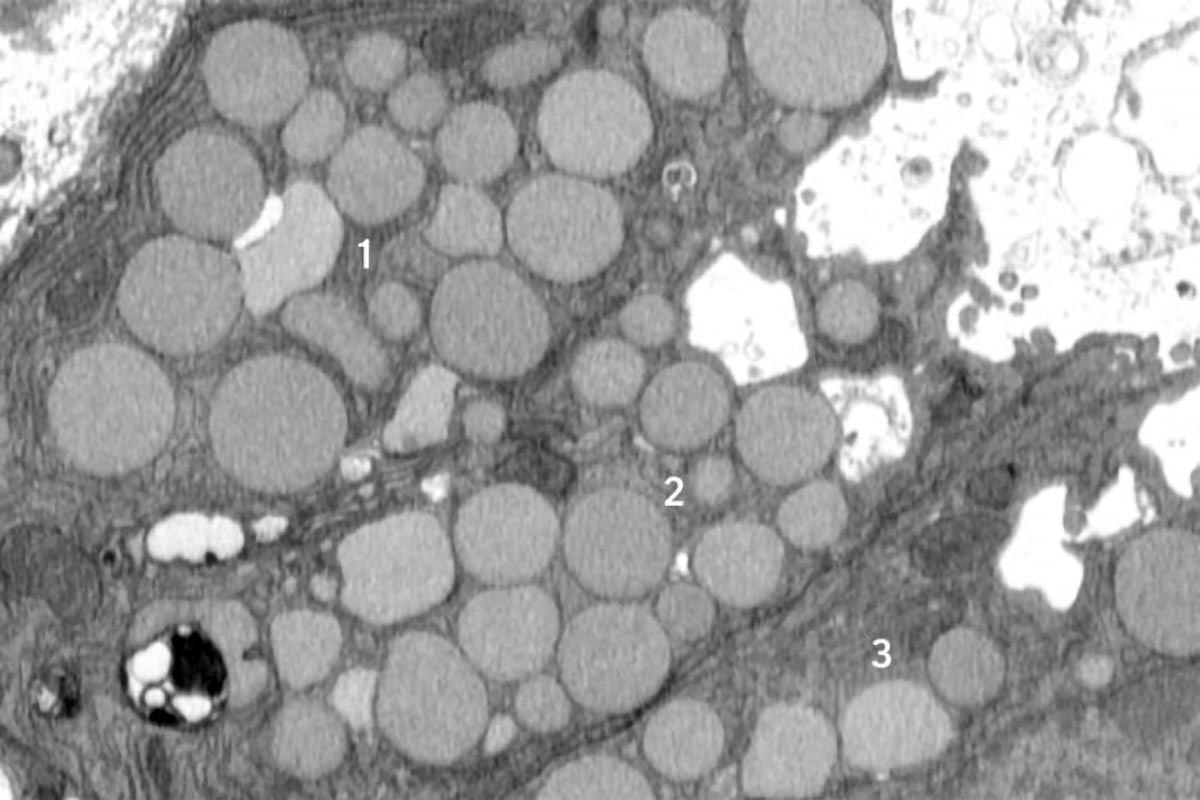

A new study reveals that injured cells can rapidly expel waste through a process called cathartocytosis to accelerate healing, a mechanism that may also increase cancer risk but could help in early detection of precancerous conditions.